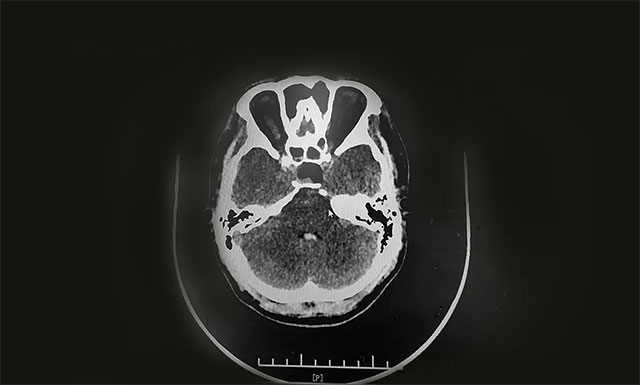

▲ 术后CT显示肿瘤被切除